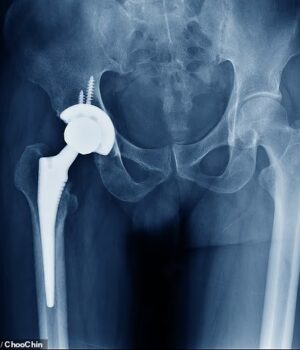

Alguns cimentos de fixação padrão, Usado em cirurgia ortopédica para fixar articulações artificiais com segurança ao osso, geralmente em substituições de quadril e joelho.

O cimento atua como uma argamassa forte, preenchendo o espaço entre o implante metálico e o osso do paciente.

Ele foi projetado para endurecer rapidamente e criar uma ligação estável para manter o novo implante firmemente no lugar.